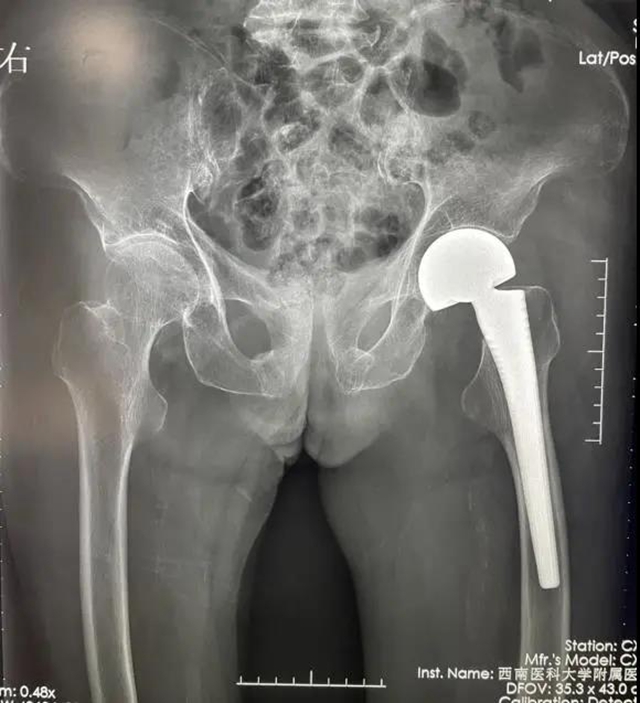

第一次手术,术前X片检查

何婆婆到西南医大附院检查后,确诊为左侧股骨颈骨折、心率失常,伴发肺部感染、胸腔积液、尿路感染等长期卧床并发症。

骨与关节外科后立即采用多学科协作模式(MDT),综合评估与讨论患者情况,采用ERAS(加速康复外科)理念,经过快速缜密充分的术前准备,于入院48小时内,由谭美云教授为患者施行左侧人工股骨头置换手术,手术过程顺利,手术时间约为30分钟,术中出血量约为50ml左右。